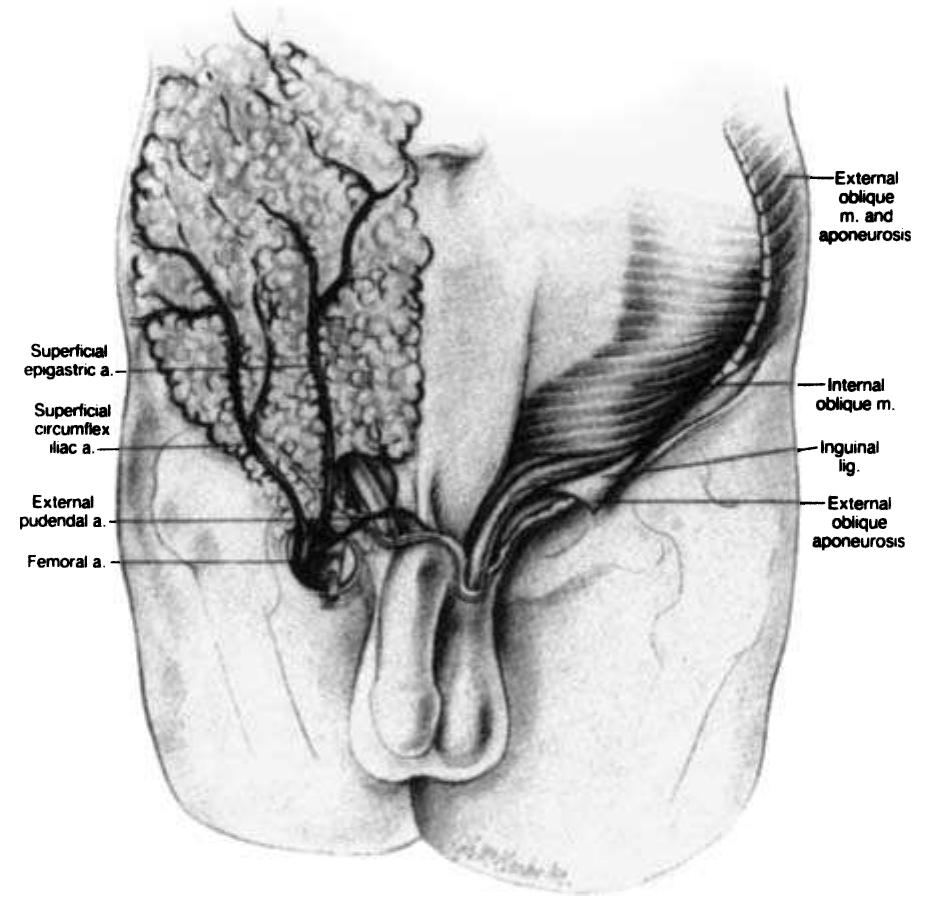

- The external iliac artery becomes the common femoral artery as it emanates from a point under the middle of the inguinal ligament.